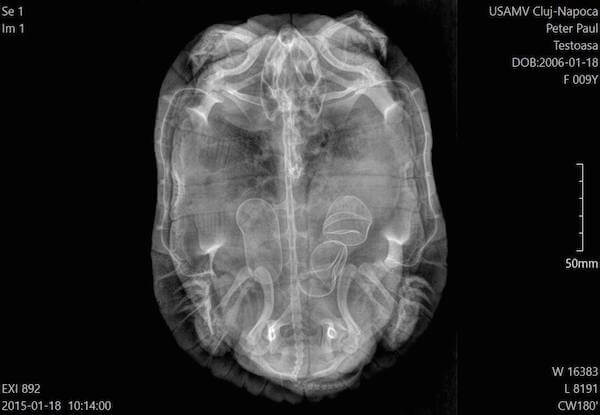

Broasca testoasa de apa - 2 indivizi distincti, cu retentie oua - expunere VD si expunere caudo-craniana. Umbra oului este vizibila. Examinarea radiologica este cel mai bun mod de a evalua retentia oului la testoasa.